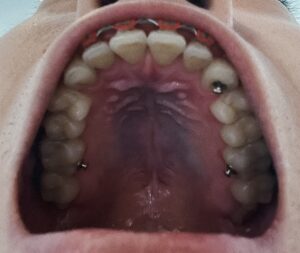

歯並びの変化(写真あり)

歯並びの変化を写真で載せていきます。

<上の歯並び>

【2025年10月25日】